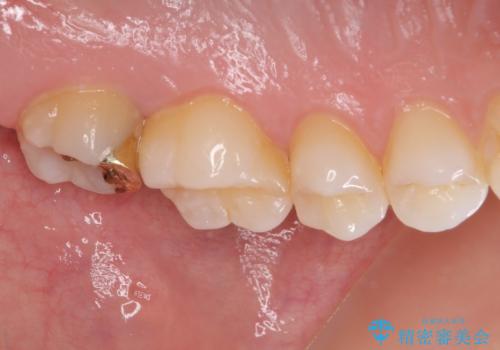

- 奥歯にフロスが引っかかるようになり、虫歯ではないかとのことで来院された患者様です。

レントゲン写真より、1番奥の歯に虫歯があることが分かりました。

奥で目立たないことから、虫歯の再発リスクが最も低く、咬合力による歯への負担も少ないゴールドインレー(PGAインレー、白金加金インレー)にて修復治療をすることとしました。